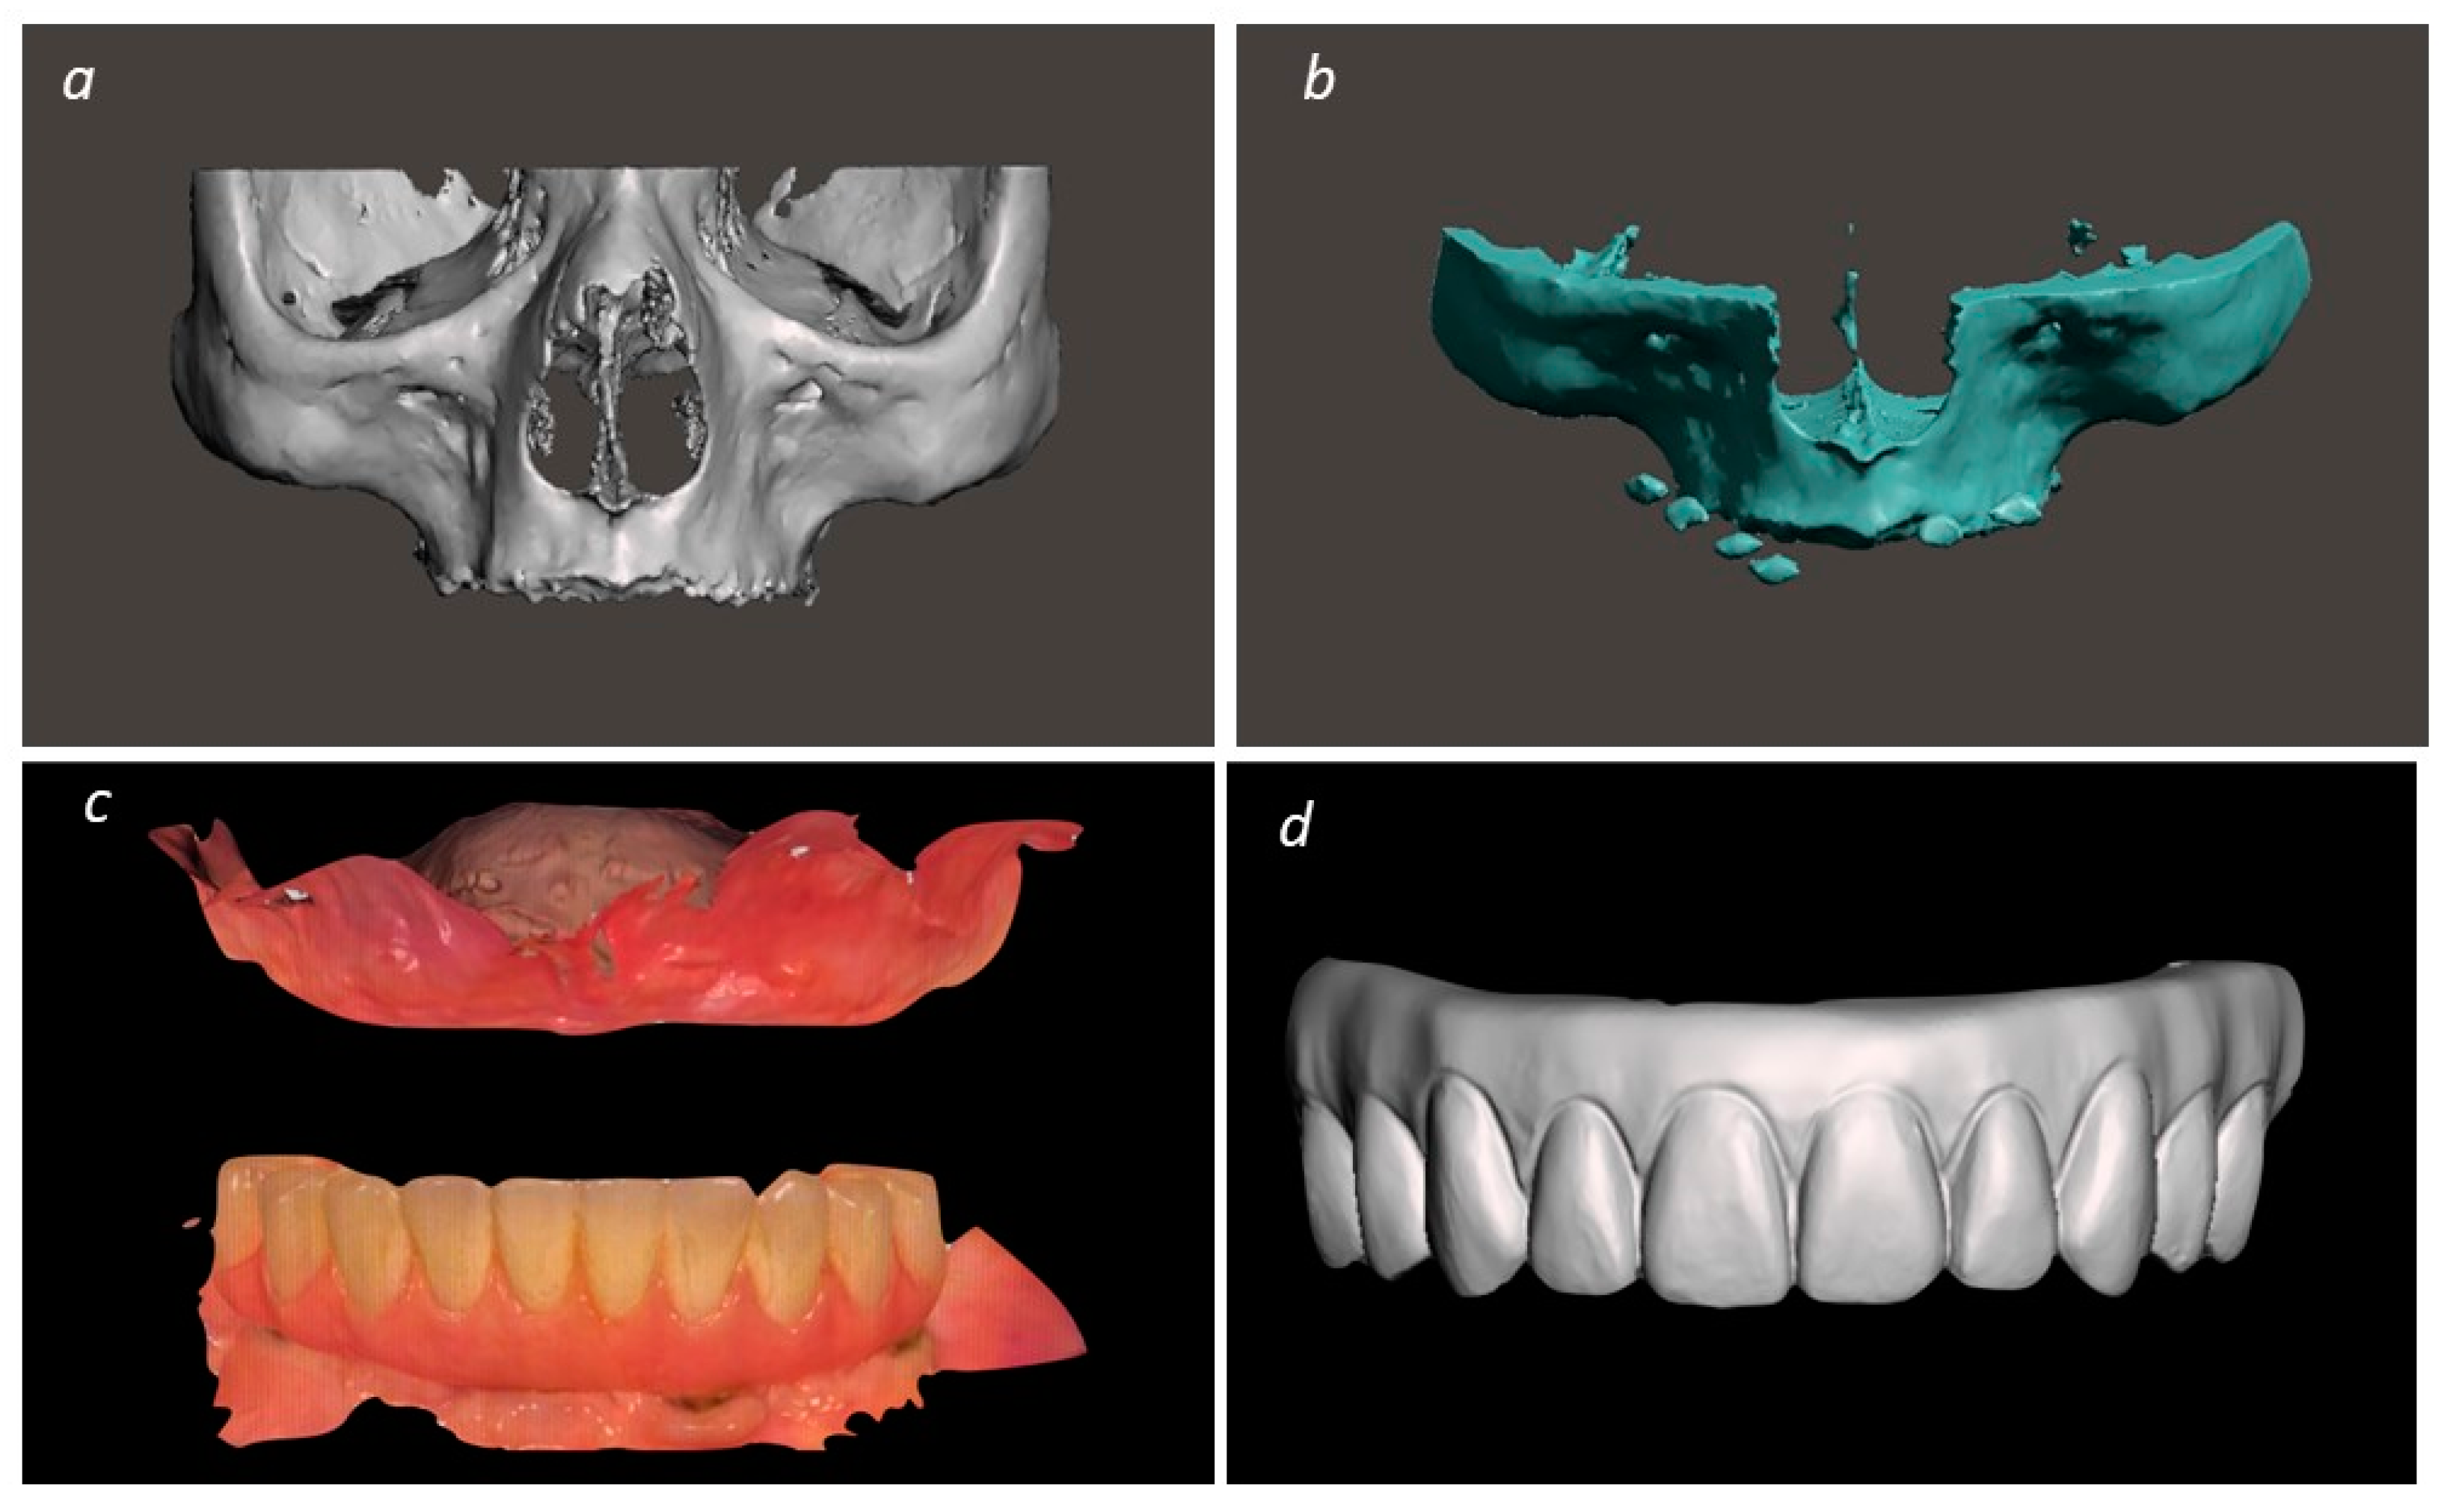

2. Materials and Methods

Description of the Technique

3. Results